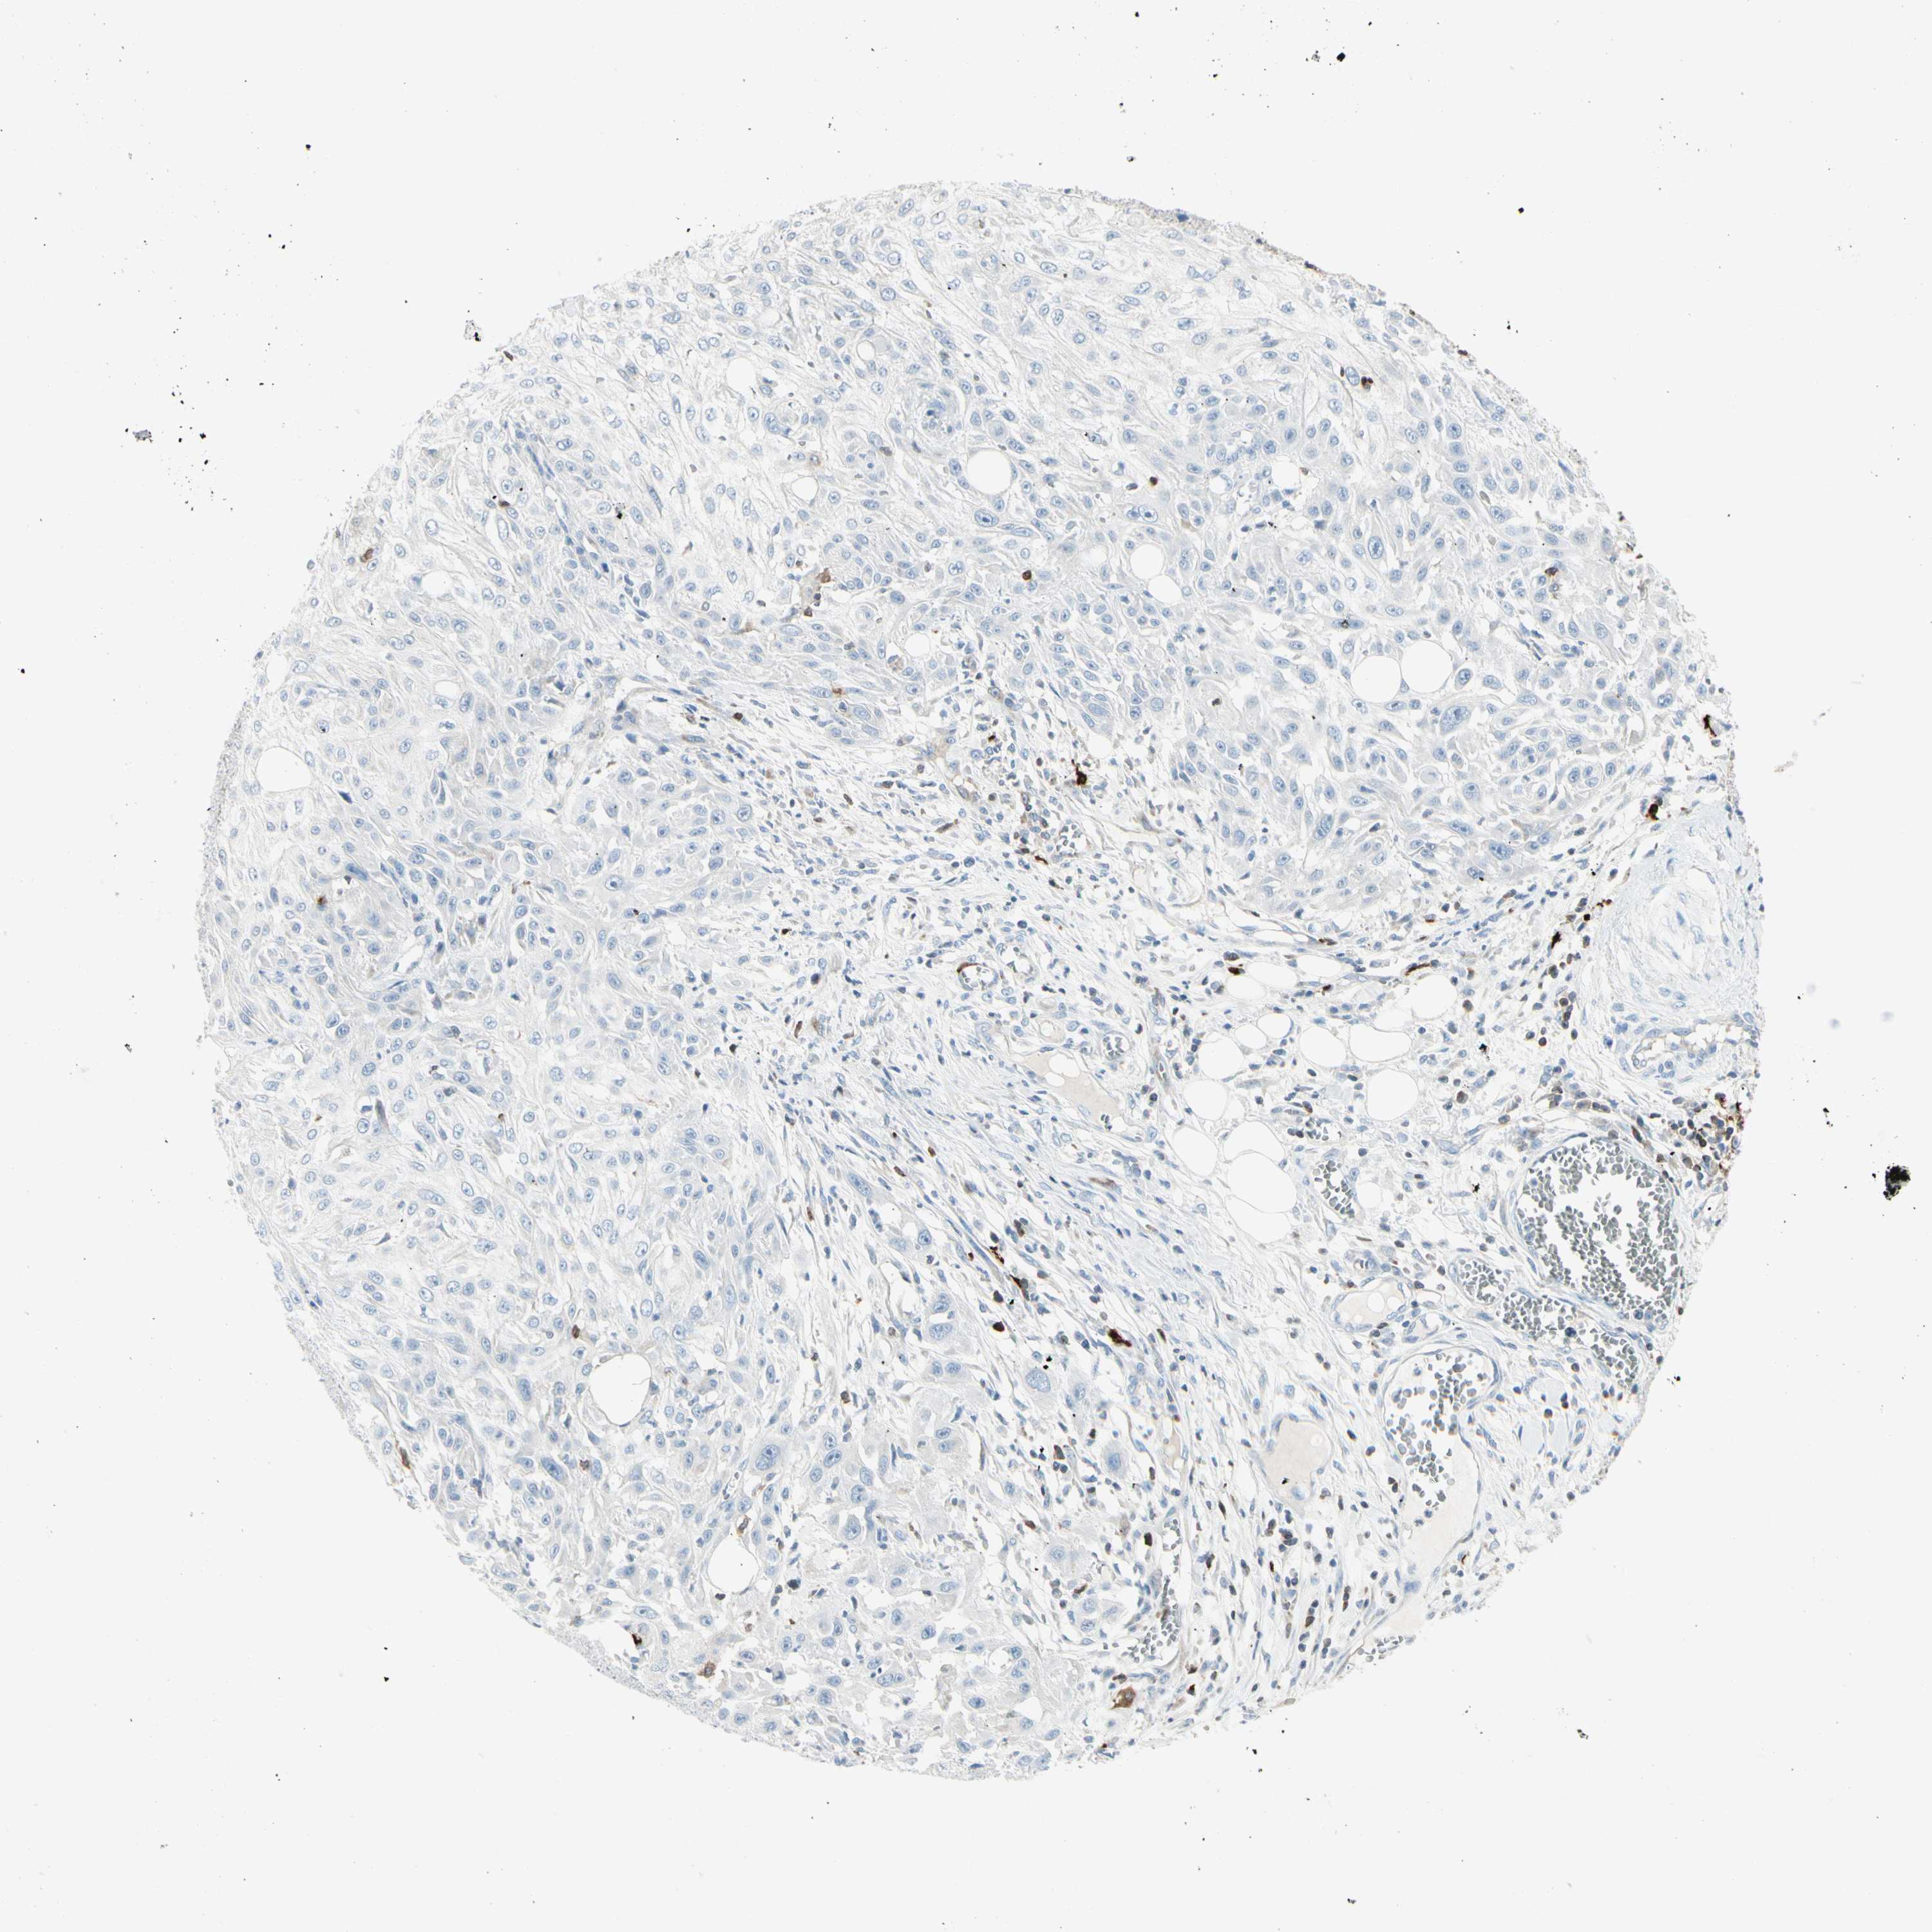

SKIN CANCER - Protein expressioni

A mouse-over function shows sample information and annotation data. Click on an image to view it in a full screen mode. Samples can be filtered based on level of antibody staining by selecting one or several of the following categories: high, medium, low and not detected. The assay and annotation is described here.

Each image is clickable and will lead to virtual microscopy that enables deeper exploration of all samples and also displays staining intensity scores, fraction scores and subcellular localization as well as patient and tissue information for each sample.

Antibody CAB009593

Squamous cell carcinoma, NOS

Basal cell carcinoma